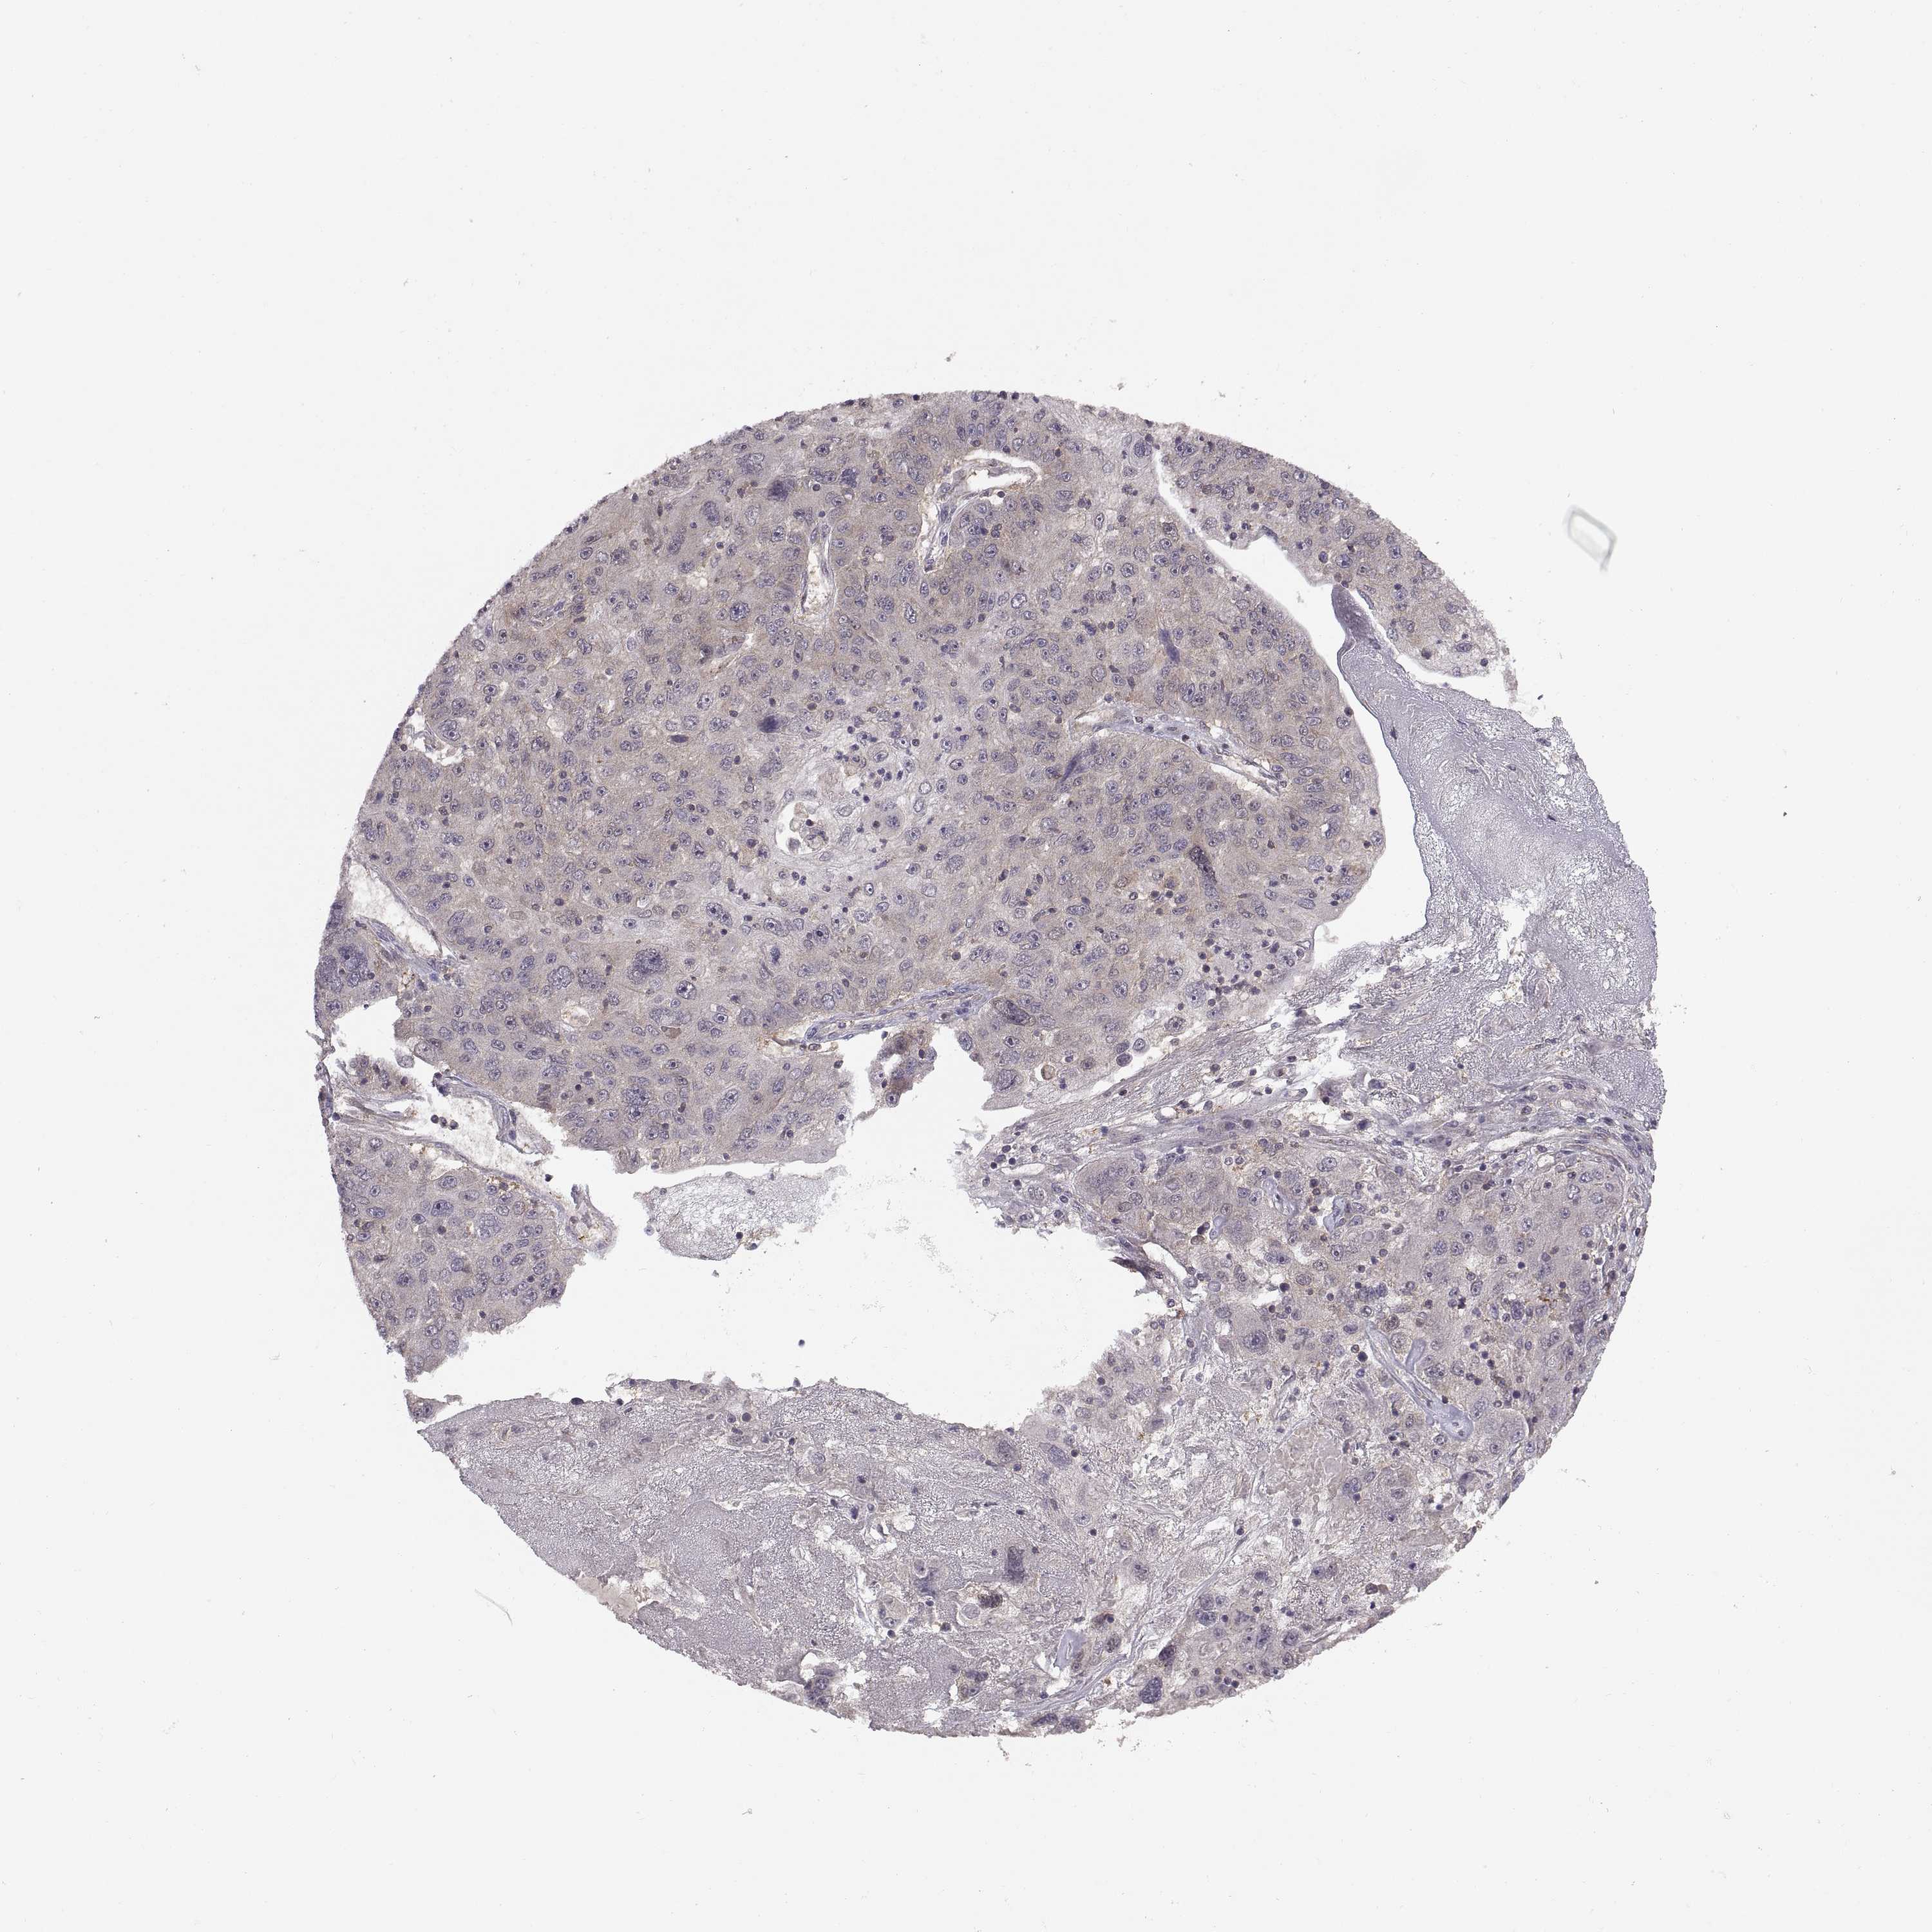

STOMACH CANCER - Protein expressioni

A mouse-over function shows sample information and annotation data. Click on an image to view it in a full screen mode. Samples can be filtered based on level of antibody staining by selecting one or several of the following categories: high, medium, low and not detected. The assay and annotation is described here.

Note that samples used for immunohistochemistry by the Human Protein Atlas do not correspond to samples in the TCGA dataset.

Antibody stainingi

Antibody staining in the annotated cell types in the current human tissue is reported as not detected, low, medium, or high, based on conventional immunohistochemistry profiling in selected tissues. This score is based on the combination of the staining intensity and fraction of stained cells.

Each image is clickable and will lead to virtual microscopy that enables deeper exploration of all samples and also displays staining intensity scores, fraction scores and subcellular localization as well as patient and tissue information for each sample.

Antibody HPA061714

Staining

High

Medium

Low

Not detected

Intensity

Strong

Moderate

Weak

Negative

Quantity

>75%

75%-25%

<25%

None

Location

Nuclear

Cytoplasmic/membranous

Cytoplasmic/membranous,nuclear

Adenocarcinoma, NOS